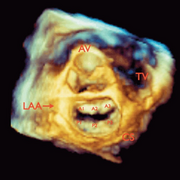

We are investigating the differences that exist between normal and abnormal cardiac valves, specifically by using echocardiographic data to describe valvular morphology and dynamism over the cardiac cycle both qualitatively and quantitatively

One of our current focuses is a tricuspid annular analysis. We are examining the structural changes of the tricuspid annulus over the cardiac cycle. Our current methodology is being applied to both normal and abnormal annuli. We have also demonstrated the ability to prototype patient-specific annuli using CAD software and 3D printing.

Khurram Owais, MD, Charles E. Taylor, PhD, Luyang Jiang, MD, Kamal Khabbaz, MD, Mario Montealegre-Gallegos, MD, Robina Matyal, MD, Joseph H. Gorman III, MD, Robert C, Gorman, MD, Feroze Mahmood, MD. Tricuspid Annulus: A Three-Dimensional Deconstruction and Reconstruction. Ann Thorac Surg. 2014; 98:1536-43)